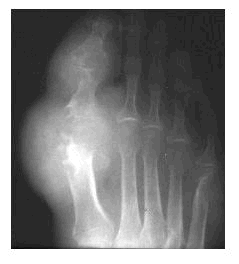

When it crystallizes, uric acid takes on a shape like that of a needle, and like a needle, it jabs its way into the joints. It seems to prefer the joint of the big toe, but other joints can be vulnerable as well, including the mid-foot, ankle, knee, wrist and even the fingers.

Acute pain is usually the first symptom. The affected joints then become inflamed and almost infected-looking – red, swollen, hot and extremely sensitive to the touch. Over time, this can harm the joints, tendons, and other tissues.